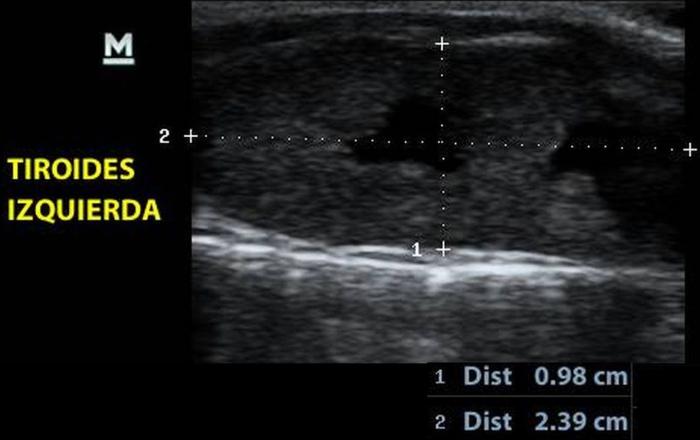

La glándula tiroides en perros y gatos está constituida por dos lóbulos situados a ambos lados de la tráquea cervical, con disposición longitudinal y una forma fusiforme o alargada que se extiende desde el cartílago cricoides hasta la entrada torácica superior2. En condiciones normales, cada lóbulo presenta contornos bien definidos, cápsula hiperecogénica delgada y parénquima homogéneo, con una ecogenicidad generalmente igual o ligeramente superior al músculo esternohioideo adyacente3,8. En la imagen transversal, los lóbulos suelen adoptar una configuración oval o ligeramente triangular (Figura 1); en longitudinal, se observa una forma alargada con extremos redondeados y orientación paralela a los vasos carotídeos y la tráquea1 (Figura 2).

En cuanto a los parámetros ecográficos de referencia, estudios realizados en perros han determinado que los lóbulos tiroideos sanos presentan una longitud entre 13-23 mm, ancho de 3-8 mm y alto de 2-5 mm, con variaciones según raza y tamaño corporal6. En gatos, las dimensiones normales son más pequeñas y oscilan entre 10-17 mm de largo, y 2-4 mm de ancho y alto, dependiendo de la edad y el estado funcional10 (ver además la Tabla 1).

El índice TG/CCA es una herramienta ecográfica cuantitativa propuesta para la evaluación del tamaño tiroideo en perros, particularmente útil cuando se sospecha de hipoplasia glandular o hipotiroidismo12. Este índice se calcula mediante la medición del área transversal del lóbulo tiroideo (TG) y la comparación con el área de la arteria carótida común (CCA) adyacente, ambas obtenidas en un corte transversal a nivel medio cervical8.

Para su obtención, el animal se posiciona en decúbito dorsal con el cuello extendido. Se utiliza un transductor lineal de alta frecuencia (mínimo 10 MHz), y se realiza una imagen transversal donde se identifican claramente el lóbulo tiroideo y la arteria carótida. Se mide el área de cada estructura mediante trazo elíptico o libre, dependiendo de la morfología. La relación se expresa como TG/CCA, un valor adimensional que permite estandarizar la evaluación tiroidea en animales de distinto tamaño corporal7.

En perros clínicamente sanos, se ha reportado un valor promedio de TG/CCA de 1.53 en promedio12. Valores consistentemente bajos pueden sugerir atrofia glandular o hipoplasia, siendo útiles para apoyar el diagnóstico de hipotiroidismo en pacientes con hallazgos clínicos y laboratoriales compatibles. Según Sasaki et al. (2020), si se utiliza el valor de corte <1.12, el índice TG/CCA indica hipotiroidismo con una sensibilidad del 100 %, una especificidad del 83 % y una precisión del 90 %.

Los autores realizaron un estudio en el que midieron el diámetro anteroposterior de los lóbulos tiroideos y el diámetro externo de la CCA en cortes transversales obtenidos a nivel del cuello medio. Encontraron que esta relación se mantiene relativamente constante entre razas y tamaños corporales, sugiriendo que puede ser utilizada como parámetro de referencia ecográfica. Específicamente, en perros adultos sanos, la relación TD/CCA fue de 1.74 ± 0.40 (rango 1.11–2.43)6. Si los valores se encuentran por debajo del rango normal pueden ser considerados potencialmente indicativos de hipoplasia tiroidea o atrofia glandular.